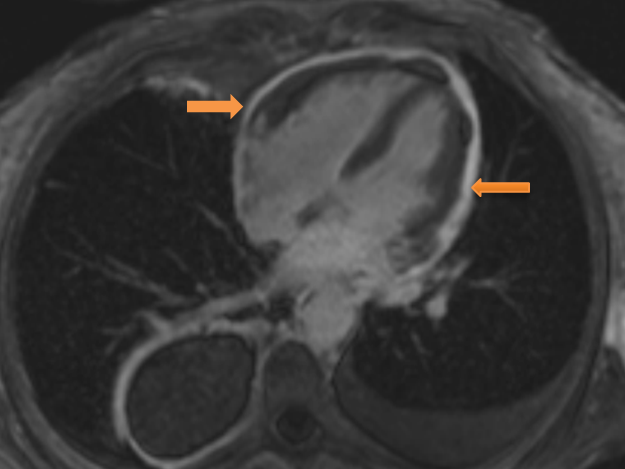

The diagnosis was confirmed on cardiac magnetic resonance (CMR) imaging with gadolinium. There was early gadolinium enhancement consistent with acute/active inflammation, coupled with diffusely thickened pericardium (8mm) and ventricular interdependence on cine images consistent with constrictive pericarditis. LV ejection fraction was normal. (Figures 3 and 4)

Figure 4: CMR phase sensitive inversion recovery delayed enhancement image in four chamber view showing diffuse circumferential pericardial enhancement (arrows).